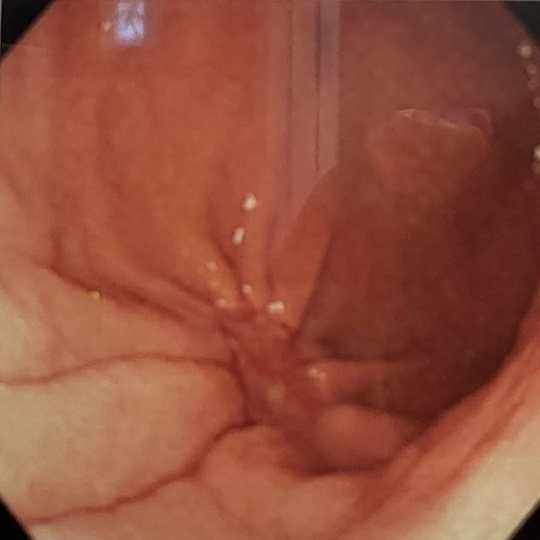

조기 위암

진행성 위암